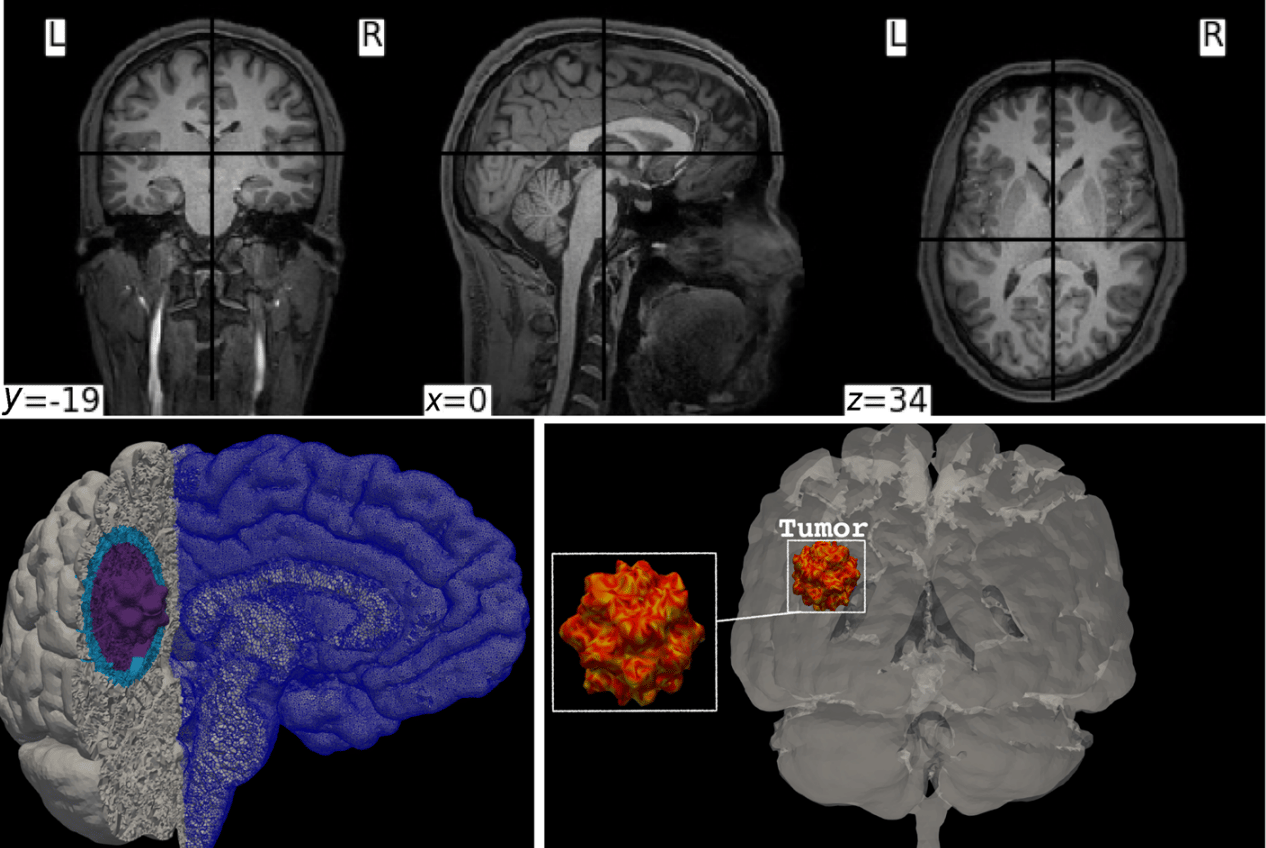

Upper panel: sample of the MRI images used to create the mesh for the cerebrum, the cerebellum, and the brainstem. Lower panel: illustration of the mesh and tumor structure. The total number of hexahedral elements is ≈ 3.289 9 × 106, and the number of DOFs is ≈ 18.949 6 × 106